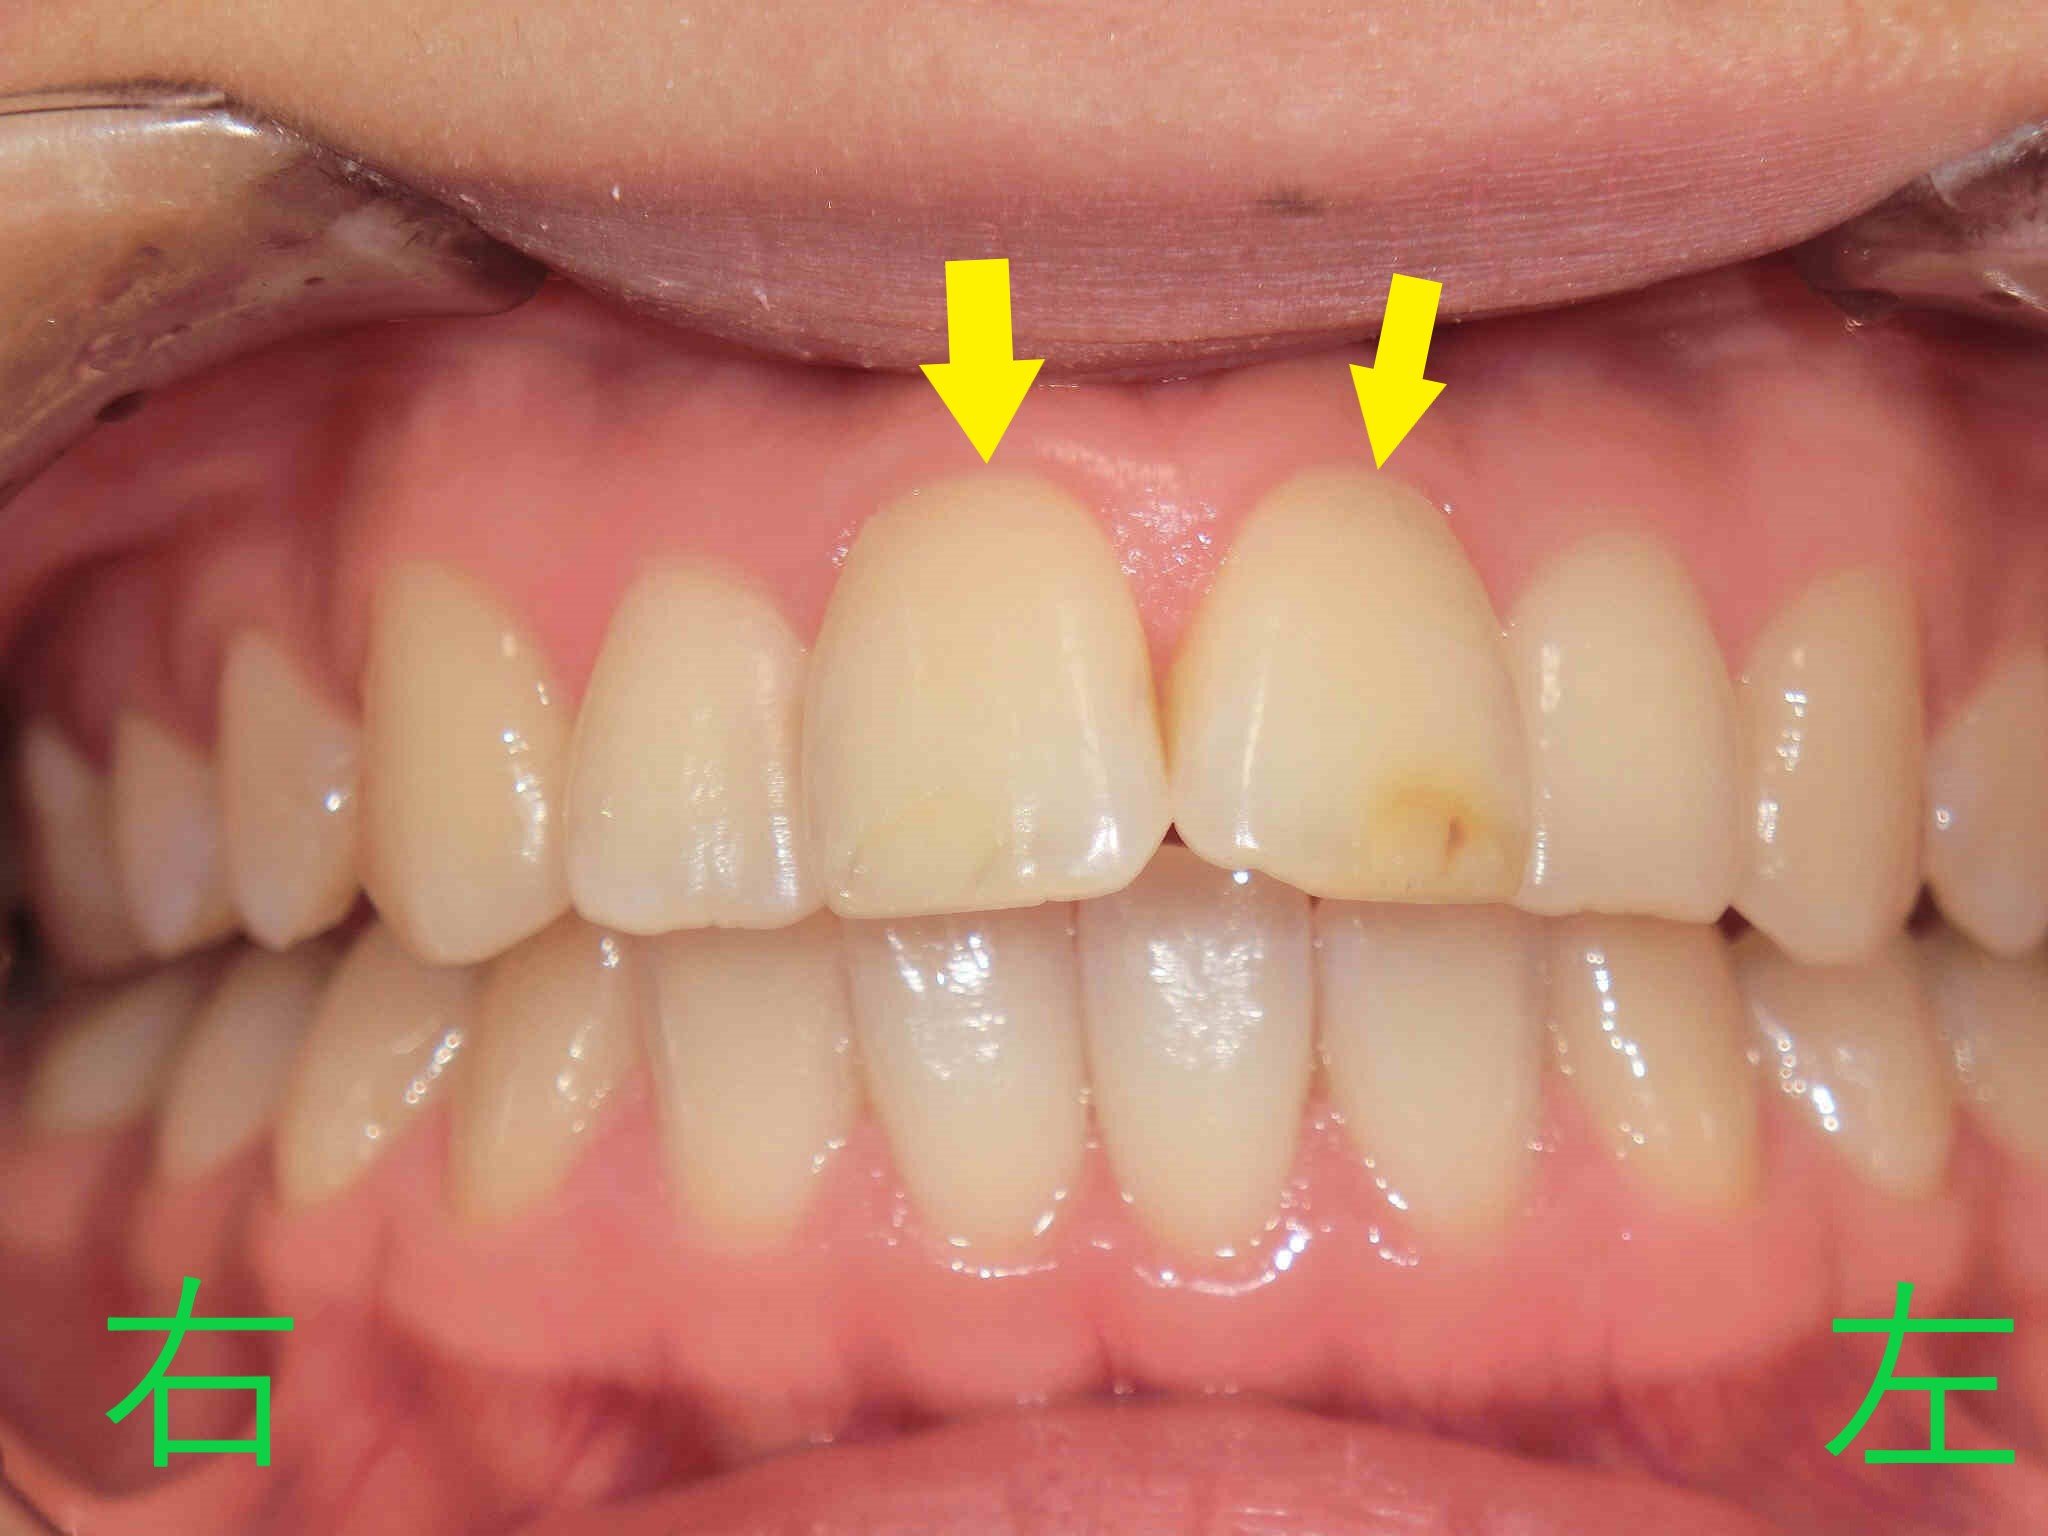

この患者様は、上顎前歯(黄色矢印)の前突(いわゆる出っ歯)を主訴として来院されました。写真からも、上顎前歯が下顎前歯と全く接触していないことが確認できます。

正面から撮影した口腔内写真でも、上顎前歯が前方に突出しており、そのために唇に力を入れないと口を閉じにくい状態であったことがわかります。